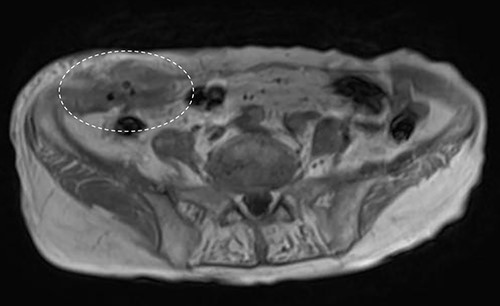

A 90-year-old woman was referred to our hospital complaining of a painful mass located in the right lower quadrant of her abdomen. She had a history of acute appendicitis, for which she underwent an appendectomy approximately 70 years prior to the current consultation. She first noticed the pain 6 months prior to consultation. In the interim, the pain gradually worsened. Upon physical examination, a palpable tumor was present below the appendectomy scar. Yellowish pus was removed from the skin over the tumor (Fig. 1). Computed tomography (CT) revealed a tumor in the abdominal wall under the surgical scar of the appendectomy (Fig. 2a). The tumor was 60 mm in width and contained a linear-shaped agent, which was thought to be a foreign body, such as a surgical needle (Fig. 2b and c). Magnetic resonance imaging (MRI) also revealed a low-signal nodule on a T1-weighted image (Fig. 3). Laboratory test results revealed no signs of inflammation. Pus culture revealed no pathogens.

Abdominal MRI showed a low-signal nodule on T1-weighted image (encircled).